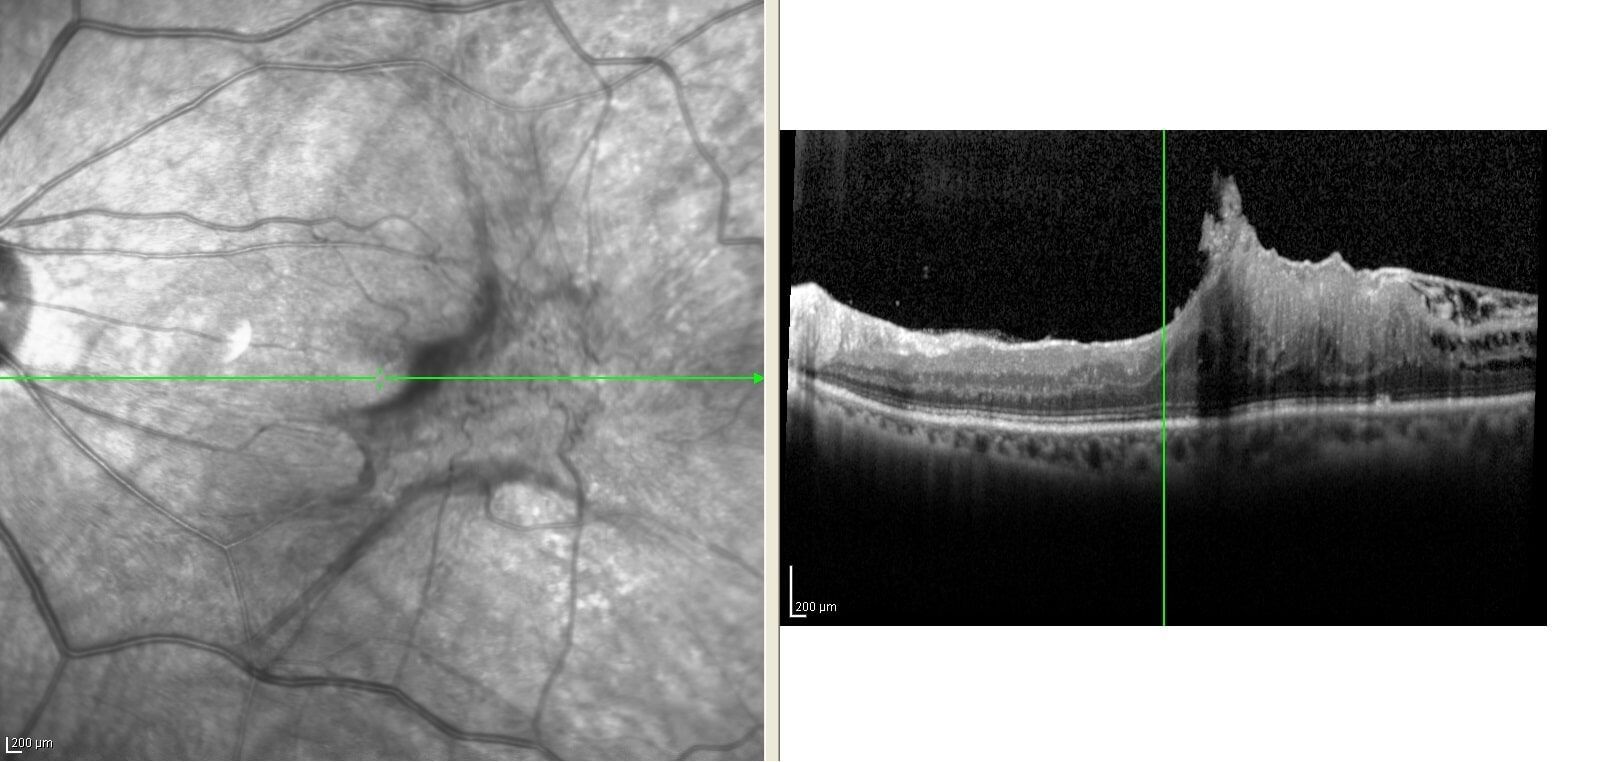

When clinically indicated, further imaging includes Optical Coherence Tomography (OCT), Fundus Fluorescence Angiography (FFA) and Indocyanide green angiography (ICG) will be done to confirm diagnosis and serve as guidance for plan of treatment.